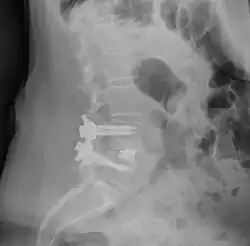

![]() Fusion of L5 and S1 | |

Spinal fusion, also called spondylodesis or spondylosyndesis, is a surgery performed by orthopaedic surgeons or neurosurgeons that joins two or more vertebrae.[1] This procedure can be performed at any level in the spine (cervical, thoracic, lumbar, or sacral) and prevents any movement between the fused vertebrae. There are many types of spinal fusion and each technique involves using bone grafting—either from the patient (autograft), donor (allograft), or artificial bone substitutes—to help the bones heal together.[2] Additional hardware (screws, plates, or cages) is often used to hold the bones in place while the graft fuses the two vertebrae together. The placement of hardware can be guided by fluoroscopy, navigation systems, or robotics.